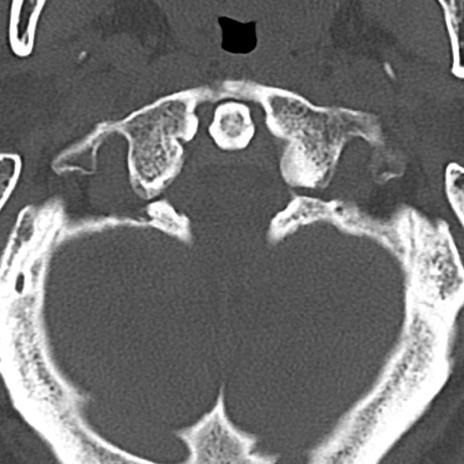

頚椎CT

横断像